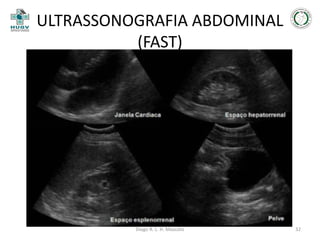

ULTRASSONOGRAFIA ABDOMINAL

(FAST)

• Objetivo;

• Sensibilidade está entre 80 a 99%;

• Vantagens;

• Desvantagens.

JAYANTHI, 2011

Diego R. L. H. Mascato

30

31

32